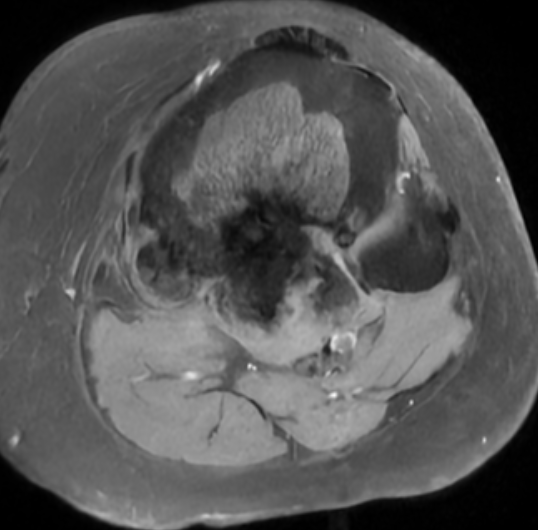

MRI

Parosteal osteosarcoma posterior distal femur

Parosteal osteosarcoma anterior tibia

Parosteal osteosarcoma posterior tibia